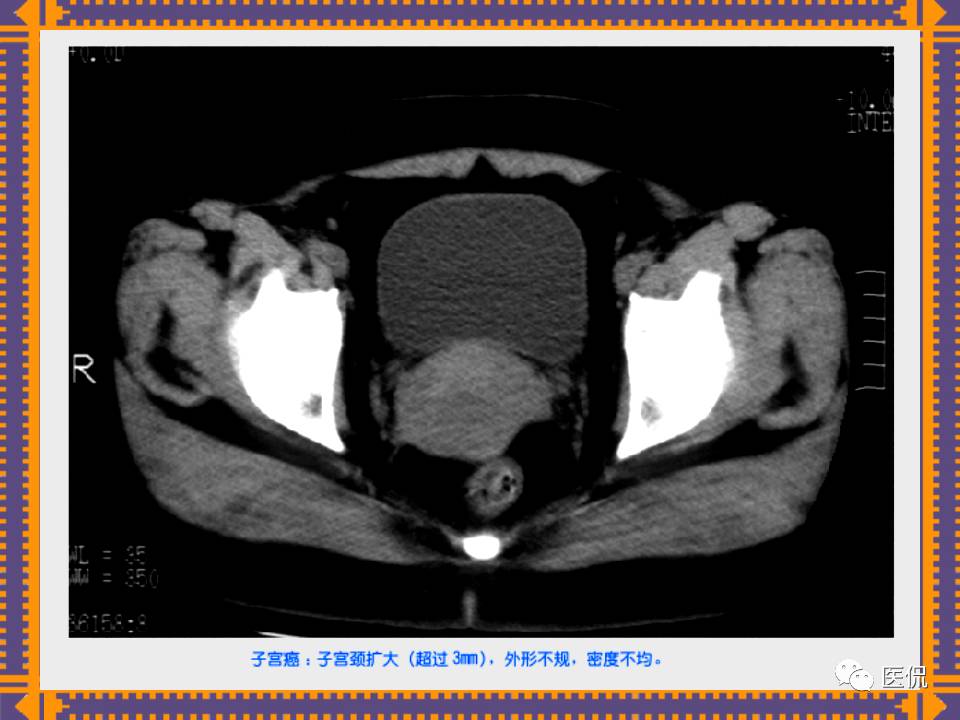

这篇PPT对男性生殖系统疾病:前列腺增生、前列腺癌;女性生殖系统疾病:子宫肌瘤、子宫癌、卵巢囊肿和卵巢肿瘤以及腹膜后间隙疾病进行了详细讲解。